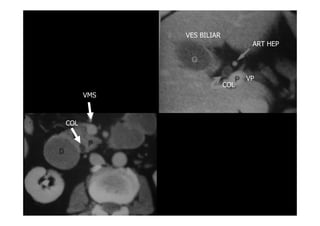

Anatomia da vesícula biliar.

• Vesícula: estrutura cística de

Vesícula: estrutura cística de

paredes finas aderida a face

infero

infero-

-medial do lobo direito

medial do lobo direito

do fígado

• Relações da V.B.:

Relações da V.B.:

figado(acima),1

figado(acima),1-

-2 porção

2 porção

duodeno(posteriormente),

cólon transverso

(inferiormente) e parede

abdominal

• divisão:corpo,colo e fundo

divisão:corpo,colo e fundo

• Vias biliares:ductos

Vias biliares:ductos

hepáticos,cístico e colédoco

ART HEP

VP

COL

VES BILIAR

VMS

PORÇÃO INTRA PANCREÁTICA DO DUCTO COLÉDOCO AO LONGO DA FACE PÓSTERO

LATERAL DA CABEÇA DO PANCREAS

TRAJETO DO COLÉDOCO ATRAVÉS DO

LIGAMENTO HEPATODUODENAL NA PORTA

HEPATIS ATÉ O DUODENO